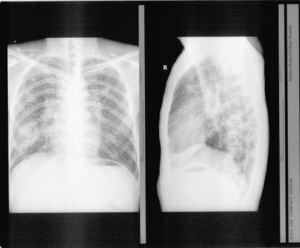

尘肺,是在职业活动中长期吸入生产性粉尘(灰尘)引起的疾病。河南新密农民工张海超怀疑自己在工厂得了尘肺,先后被多家权威医院确诊,但在(尘肺)职业病法定诊断机构——郑州市职业病防治所看病时,却被诊断为肺结核。多方求诉无效后,2009年6月22日张海超做出惊人之举,他到郑大一附院做了开胸手术,以证明自己确实患的是尘肺,不是肺结核。

尘肺影像透视